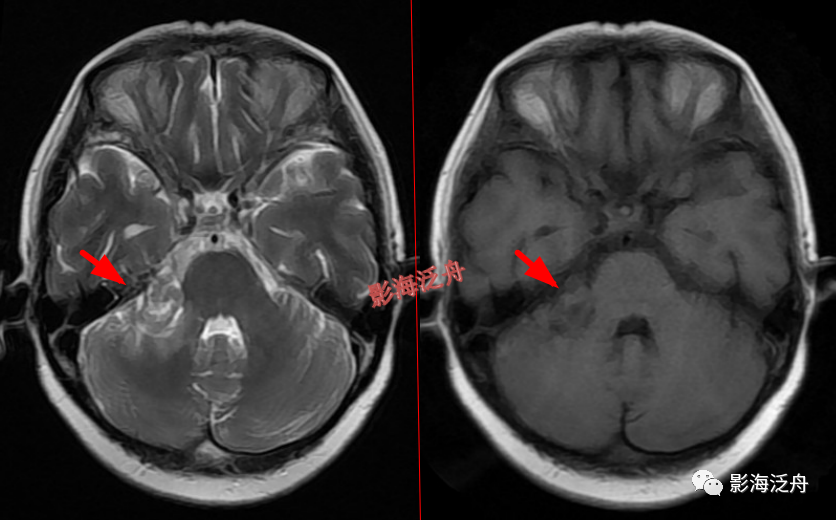

延髓左侧小梗死灶。这种斑点状的梗死灶漏诊也非常多见,患者症状一般不明显,我自己漏诊过两次。小的梗死灶多见于脑干、侧脑室周围,大脑皮层区一般不多见。因此,重点区域进行细致观察,可以减少此类疾病的漏诊。

颞极前方蛛网膜囊肿(红箭)漏诊率也比较高,尤其在老年患者中,常常被误认为是扩大的蛛网膜下间隙,仔细观察可以发现右侧颞叶受压,脑沟闭塞(绿箭),与健侧(蓝箭)对比更为明显。